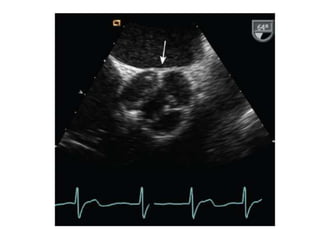

Área valvular por planimetría 2D

Paraesternal eje corto en la punta de las valvas

Puntos clave:

• Identificar el orificio de la válvula estenótica, en forma de túnel.

• El modo de zoom se utiliza para enfocar el orificio valvular, con la ganancia reducida para

mostrar claramente la interfaz tejido-sangre.

• Para obtener el área valvular, se traza el borde interior de la interfaz negro-blanco.

• Normalmente, en los pacientes sin intervenciones previas el orificio tiene una forma lisa y

elíptica.

• Tras valvuloplastía percutánea o quirúrgica, el orificio es más irregular debido a la separación

de las comisuras fusionadas.

Paso 2: Evaluarla gravedad de la EM Cont… Área valvular por planimetría 2D Paraesternal eje corto en la punta de las valvas Puntos clave: • Identificar el orificio de la válvula estenótica, en forma de túnel. • El modo de zoom se utiliza para enfocar el orificio valvular, con la ganancia reducida para mostrar claramente la interfaz tejido-sangre. • Para obtener el área valvular, se traza el borde interior de la interfaz negro-blanco. • Normalmente, en los pacientes sin intervenciones previas el orificio tiene una forma lisa y elíptica. • Tras valvuloplastía percutánea o quirúrgica, el orificio es más irregular debido a la separación de las comisuras fusionadas.